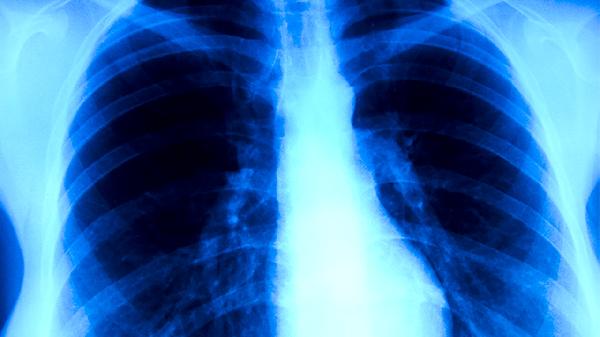

外照射放疗是最常见的放疗方式,通过体外放射源将高能射线聚焦于肿瘤部位。该技术适用于多数实体肿瘤治疗,如肺癌和乳腺癌。治疗过程中需要精确定位肿瘤位置,通常配合CT或MRI影像引导。外照射可能引起照射区域皮肤反应或疲劳等副作用,需定期评估治疗效果。

立体定向放疗采用精确定位技术进行单次或少数几次大剂量照射,主要针对脑部肿瘤和早期肺癌。通过立体定向框架或影像引导实现亚毫米级精度,具有疗程短和损伤小的特点。治疗前需进行严格的位置验证,可能出现短期头痛或恶心等反应。